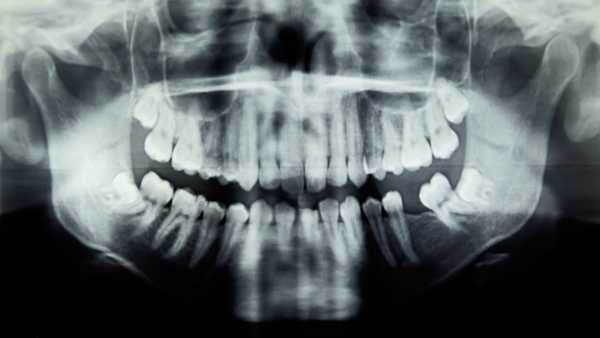

Girl’s dental trouble caused a life-threatening eye infection